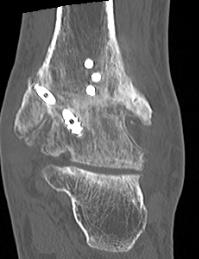

Leslie et al Foot Ankle Int 2023

- systematic review of CT confirmed union rate after ankle fusion in 237 ankles

- union rate 86%

- fix with 3 x 6.5 mm cannulated screws

- 2 medial and one lateral